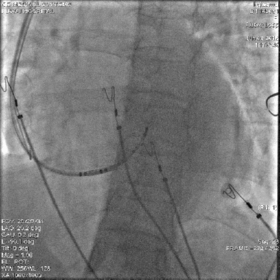

最终影像

AP

LAO

RAO